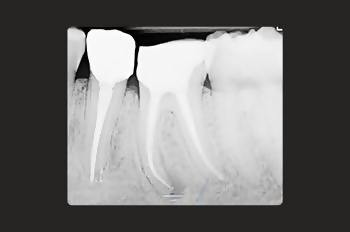

Root canal treatment is a restorative tooth-saving procedure that can avoid the need for an extraction.

Root canal treatments are a core aspect of endodontics, the dental speciality focused on treating infected tooth pulp and addressing complications from previous treatments.

Root canal treatment is needed when the tissues inside a tooth become damaged, infected, or inflamed due to deep decay, cracks, injury or repeated dental procedures on the same tooth.

Root canal treatment allows your dentist to remove the infection before it can cause irrevocable damage. It’s a tooth-saving procedure that very often saves a tooth from needing to be extracted.

Your tooth is disinfected and sealed, preventing further bacteria from compromising its structure and health.